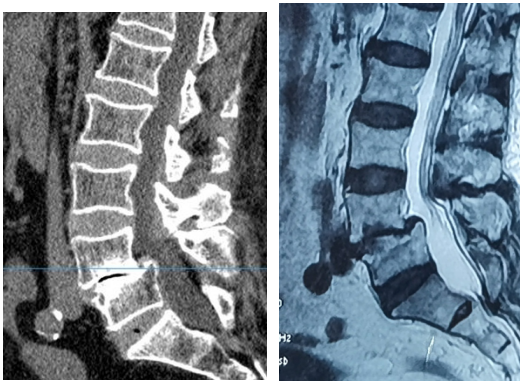

72岁的周先生,在4年前无明显诱因出现腰部酸胀不适,侧身时加重明显,伴右下肢麻木、疼痛,以右大腿后外侧、足跟较为明显,行走后加重,休息后可稍缓解。在当地医院行小针刀、针灸等对症治疗,症状稍有缓解,之后症状又反复发作。半年前症状加重,为求进一步诊治,在家人的陪同下慕名来到了海军军医大学附属长征医院脊柱外科许鹏教授处就诊。门诊腰椎MRI显示:1、腰4椎体向前I°滑脱,伴双侧峡部裂。2、腰椎退变,腰4/5、腰5/骶1椎间盘膨出,腰部皮下软组织肿胀。门诊遂以“腰椎滑脱症”收入院。

术前X片、CT、MRI